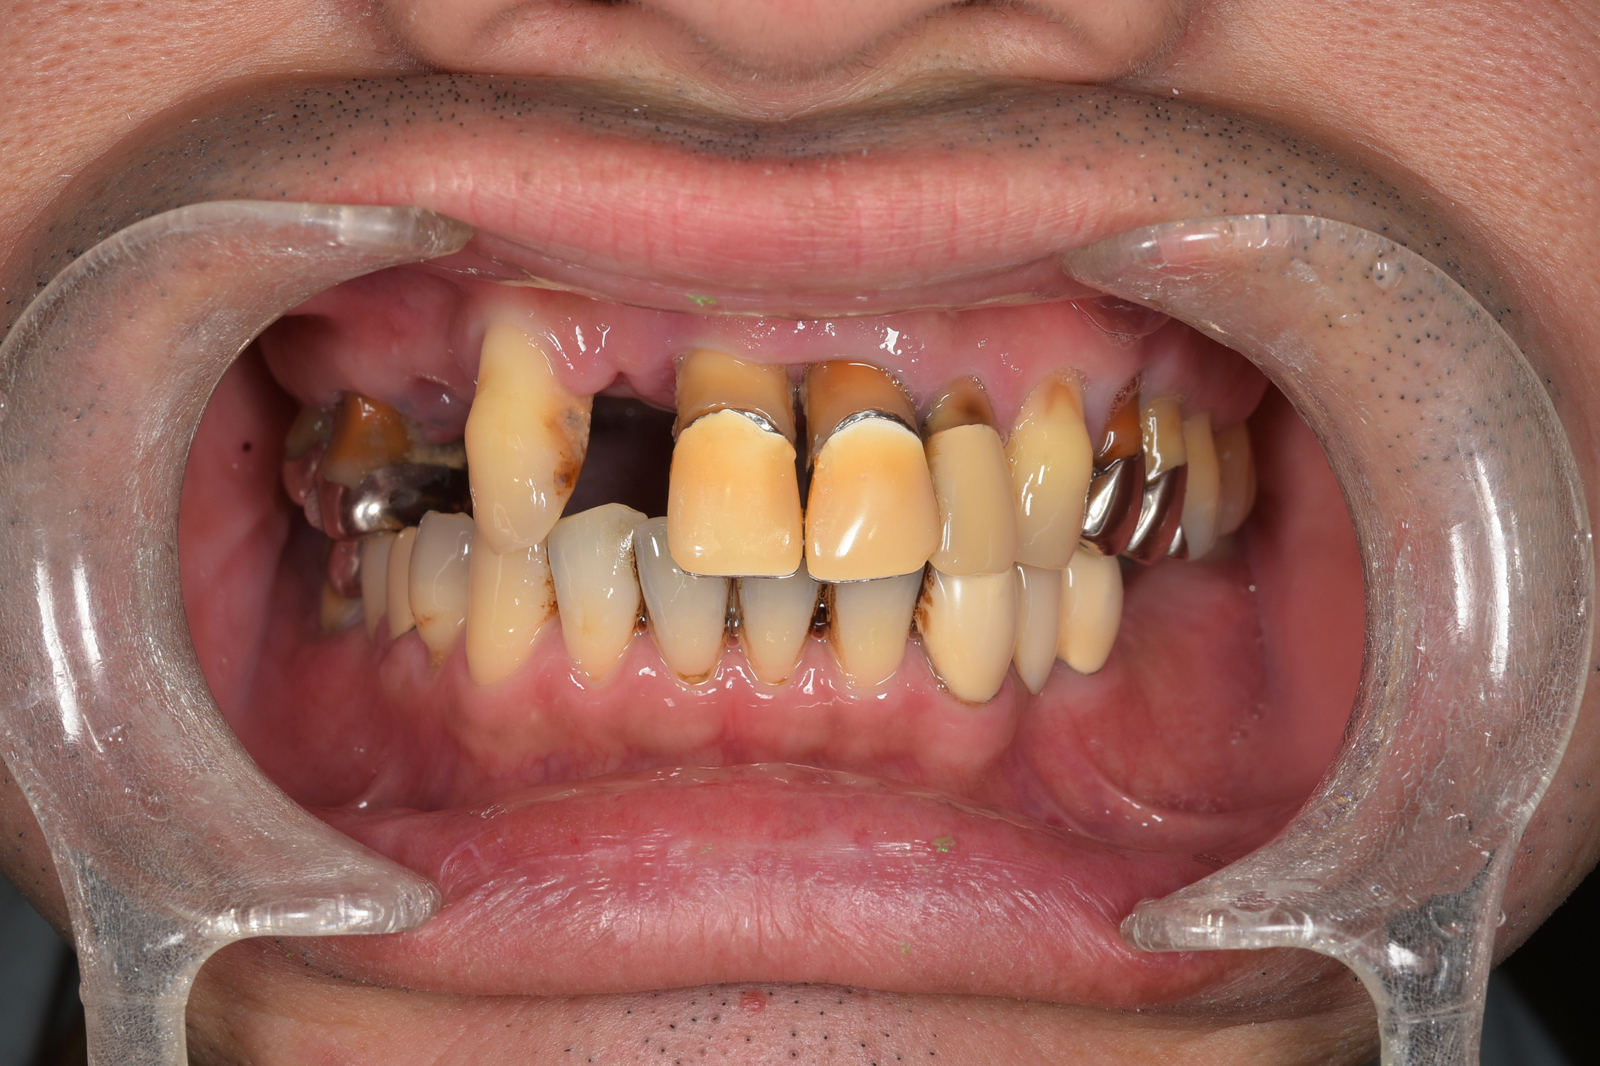

歯周病で歯が抜けてしまうのは、骨を支えている骨が溶けてしまうからです。骨を再生できれば、歯を残せる可能性が高まります。当院では、「エムドゲイン」という薬品を使って、骨の再生に取り組みます。

※症例によっては適応できず抜歯を避けられないこともあります。

エムドゲインは、特殊なたんぱく質を含む薬品です。患部を切開し、骨が失われた部分にエムドゲインを入れると、骨の再生が促進されます。個人差はありますが、数ヶ月〜1年程度で骨が再生されます。